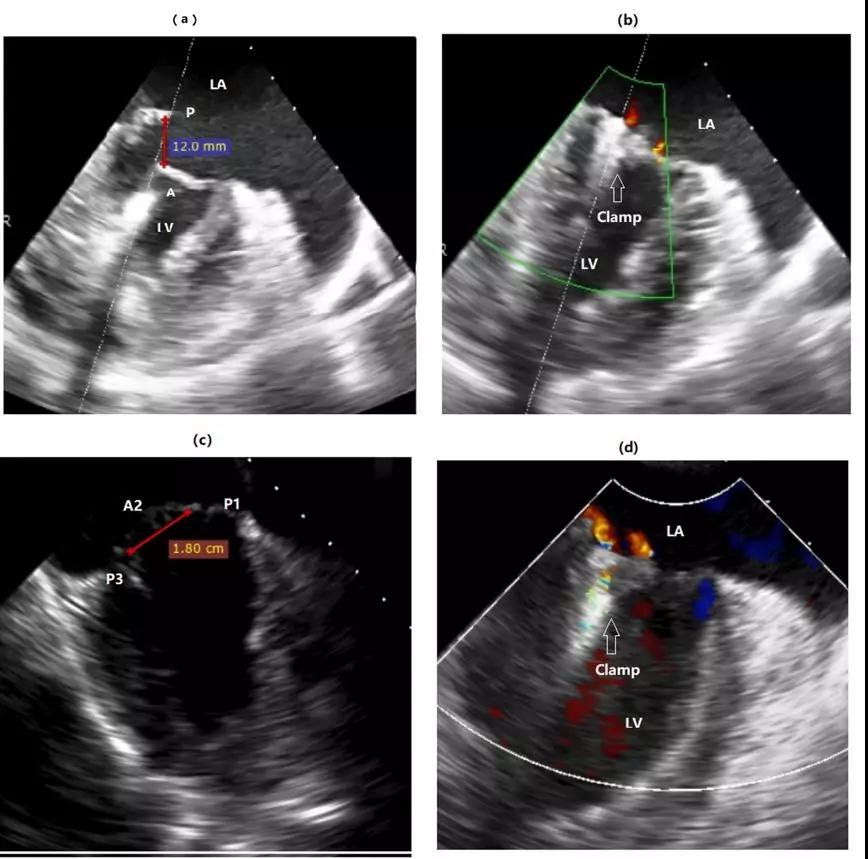

②捕获范围大,适应证广。对于瓣膜连枷非常厉害,瓣膜间歇很大患者,使用国外器械,难以同时捕获到两个瓣叶,无法完成手术,而使用ValveClamp仍可以完成手术(图2 A, B)。

③夹合稳固,效应强大。至今无一例患者发生夹子单边或者双边脱落,显示出稳固夹合效果。所有病例1个夹子即可起到很好治疗效果,而国外同类器械40%病例需要植入2个以上夹子(图2 C, D)。图2显示2例挑战性病例。

图2 2例挑战性病例术前术后心超图像